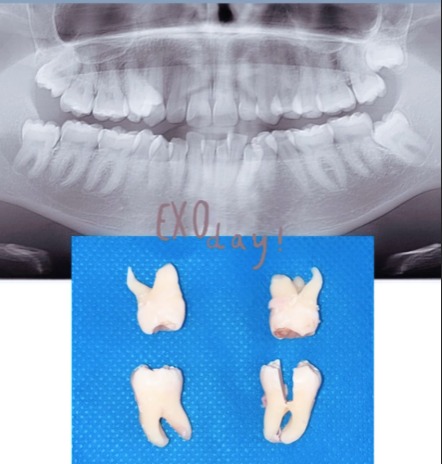

Casos de Endodoncia

En nuestras clínicas realizamos tratamientos de endodoncia con resultados comprobados, devolviendo la salud y funcionalidad a dientes afectados por caries profundas, traumatismos o infecciones. Cada paciente recibe un diagnóstico detallado, planificación personalizada y técnicas modernas que garantizan un tratamiento eficaz y cómodo.

Nuestros casos documentados muestran dientes tratados con éxito, preservando su estructura natural y restaurando la estética y la funcionalidad. Con endodoncia, evitamos extracciones innecesarias y ofrecemos soluciones duraderas que protegen tu sonrisa a largo plazo.